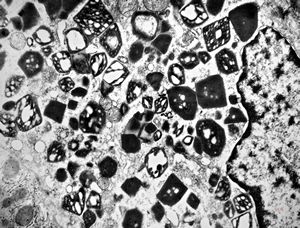

M,62y. | crystalline inclusion in endoplasmic reticulum - bone marrow, plasmocytoma

M,62y. | crystalline inclusion in endoplasmic reticulum - bone marrow, plasmocytoma

M, | crystalline inclusions in plasmocyte

M, | crystalline inclusions in plasmocyte

M,15y. | crystalline inclusion in plasmocyte - histiocyto-eosinophilic granuloma